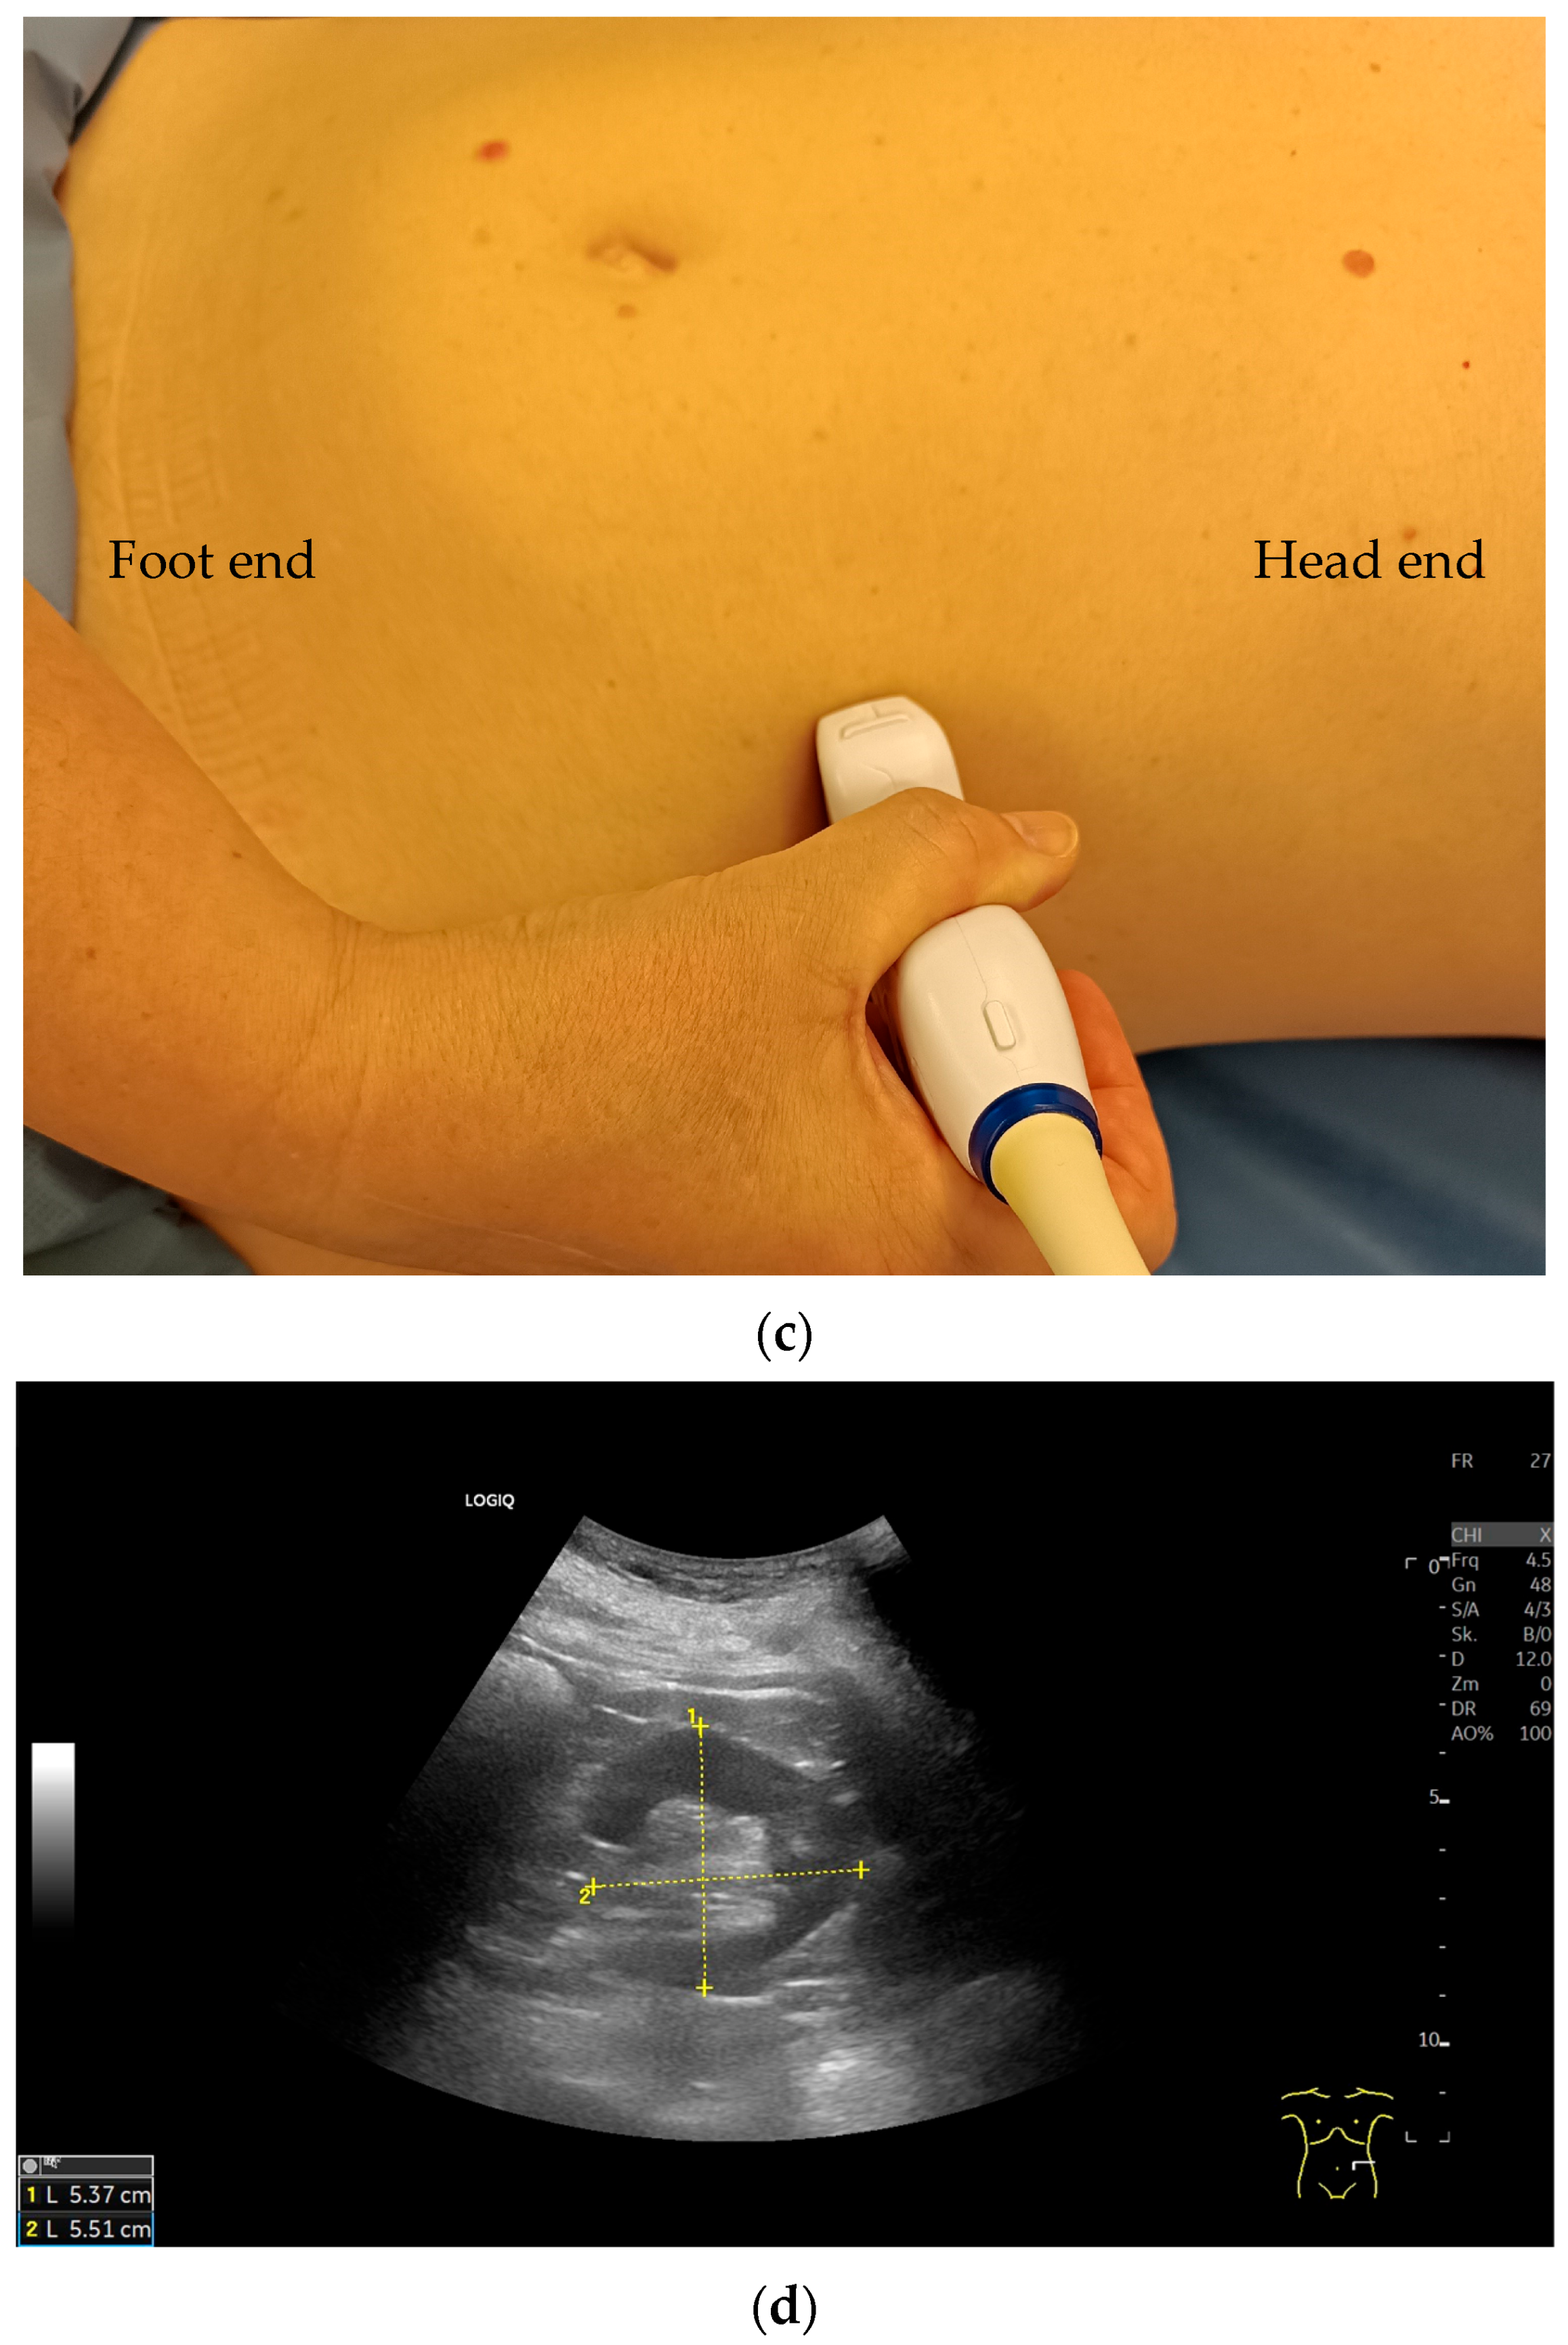

Imaging Techniques and Protocol

| Patient Position | Clinical Purpose |

|---|---|

| Supine | Opens up rib spaces to facilitate better visualization |

| Lateral decubitus | To reduce bowel gas interface |

| Oblique | In obese patients |

| Prone | Occasionally used for posterior access |

| Standing | In cases of clinically relevant suspicion of kidney descent when standing. |